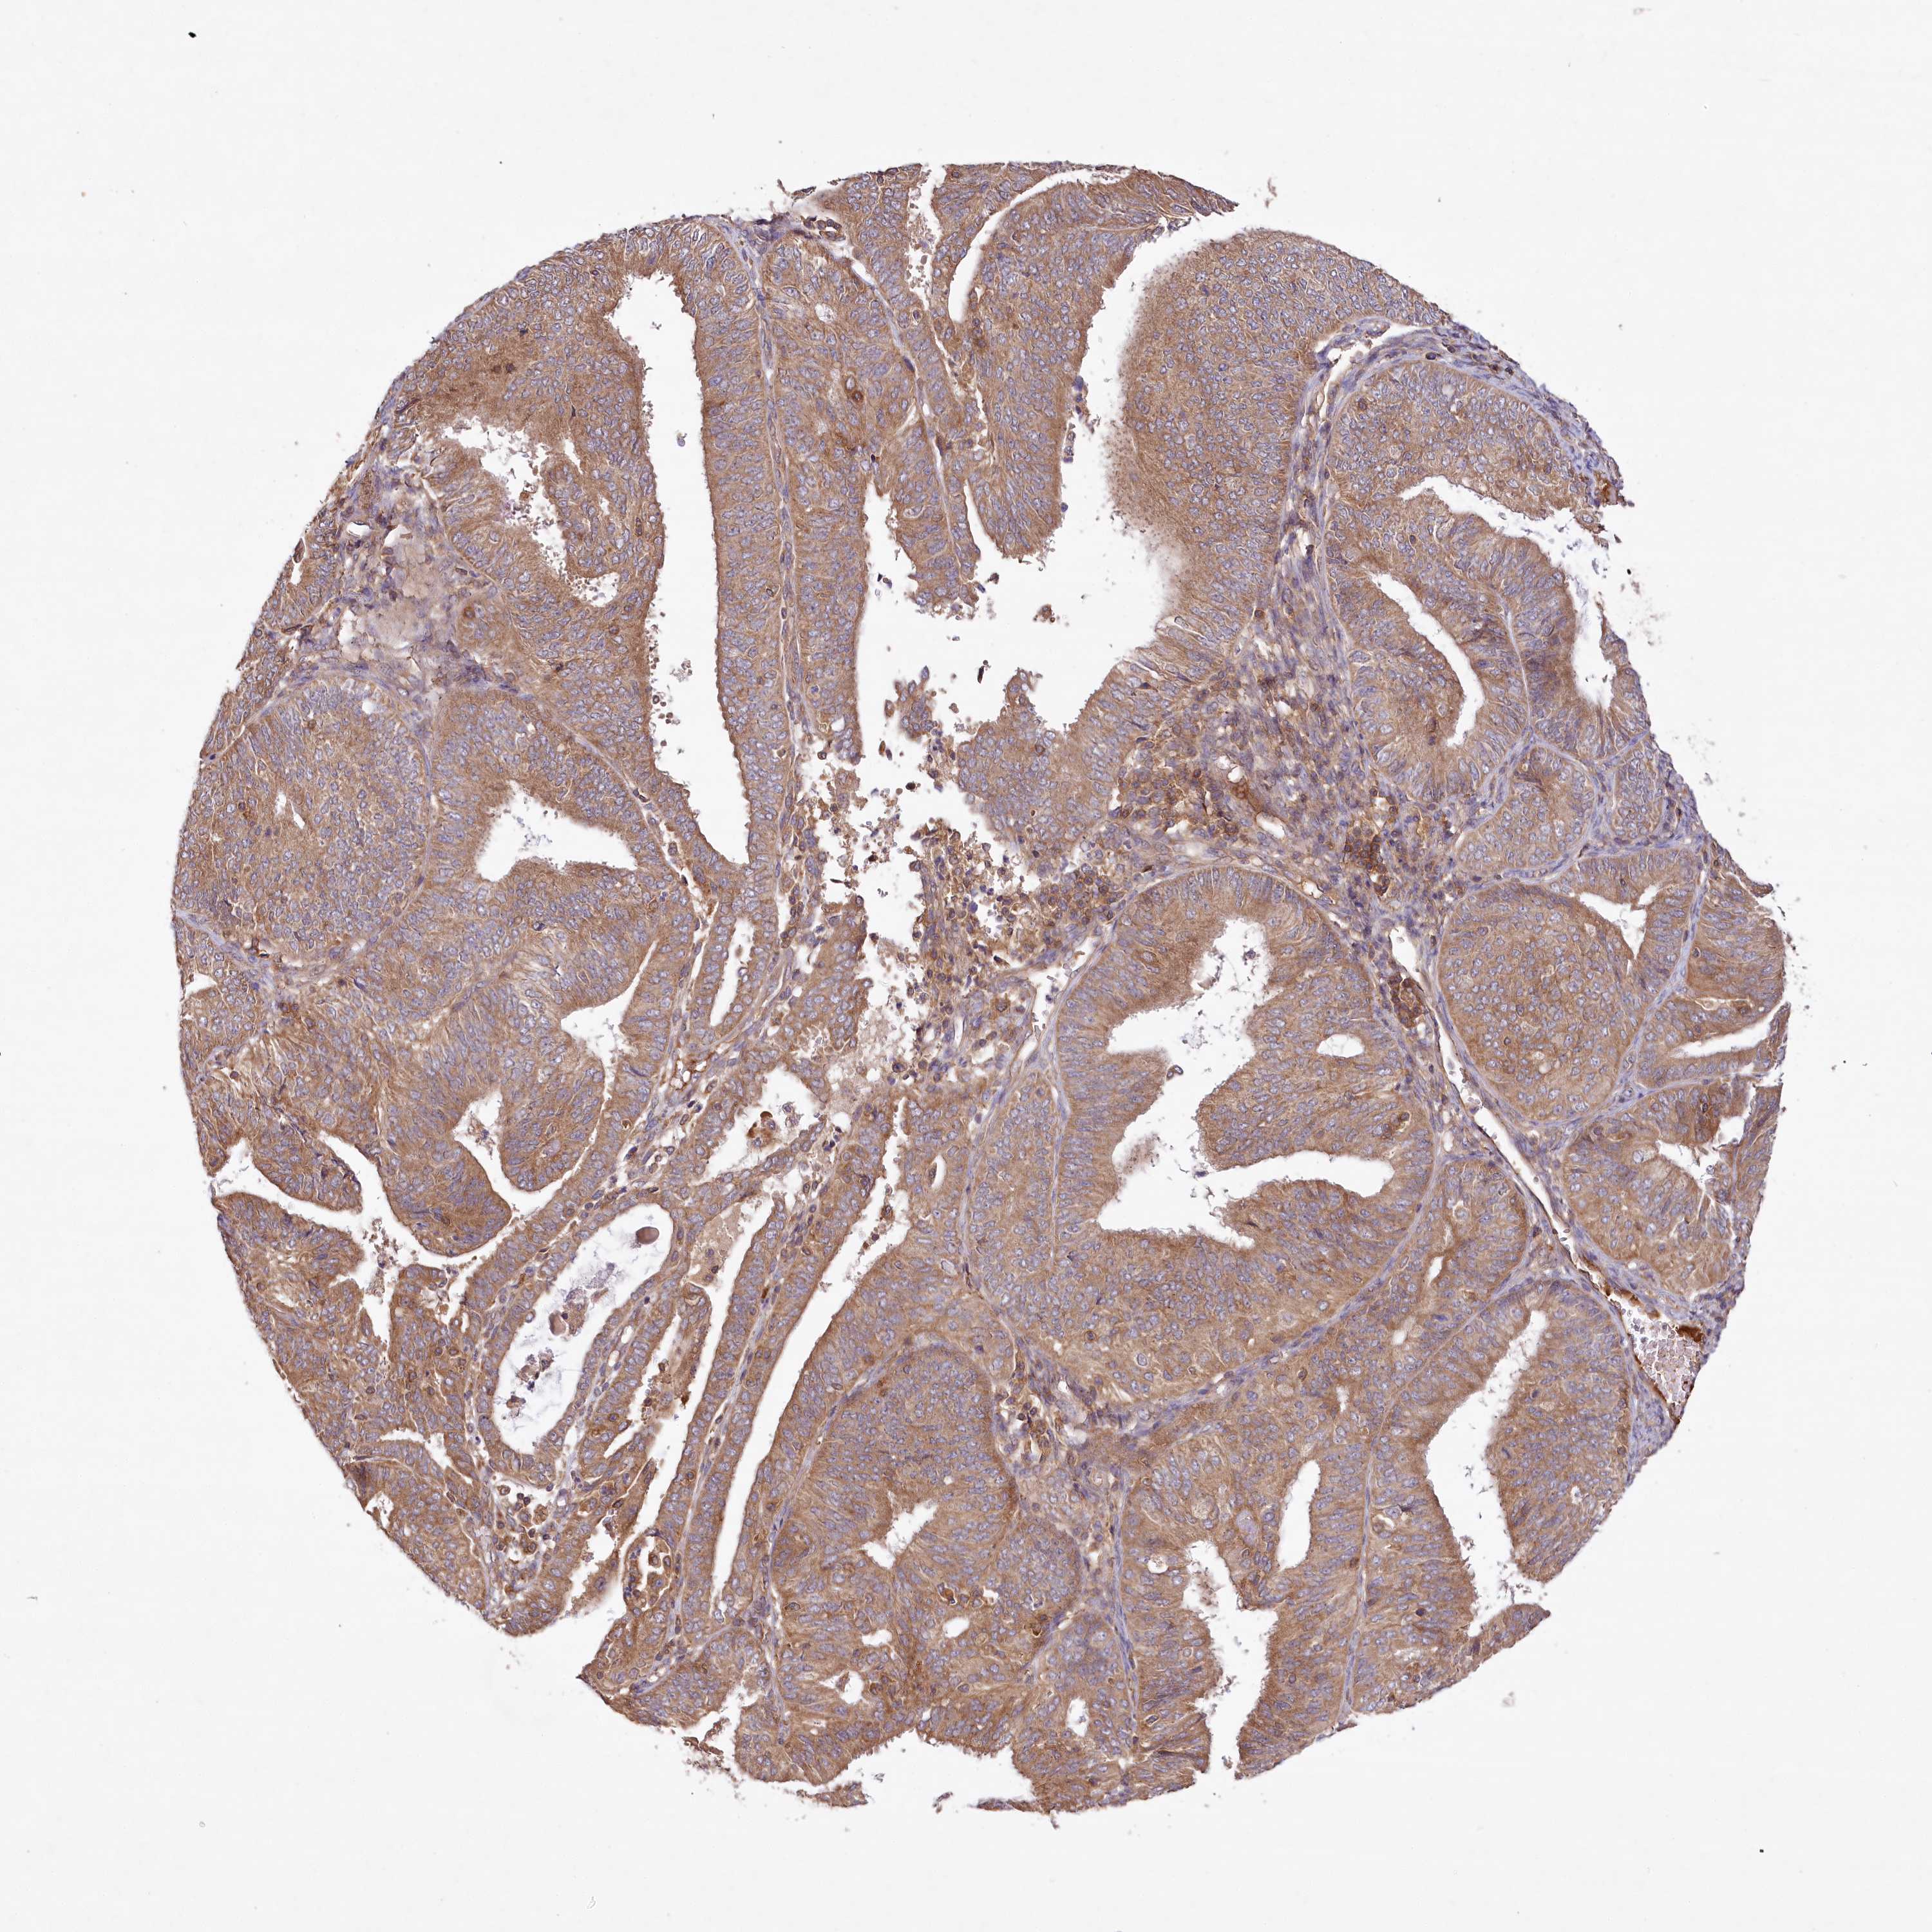

ENDOMETRIAL CANCER - Protein expressioni

A mouse-over function shows sample information and annotation data. Click on an image to view it in a full screen mode. Samples can be filtered based on level of antibody staining by selecting one or several of the following categories: high, medium, low and not detected. The assay and annotation is described here.

Note that samples used for immunohistochemistry by the Human Protein Atlas do not correspond to samples in the TCGA dataset.

Antibody stainingi

Antibody staining in the annotated cell types in the current human tissue is reported as not detected, low, medium, or high, based on conventional immunohistochemistry profiling in selected tissues. This score is based on the combination of the staining intensity and fraction of stained cells.

Each image is clickable and will lead to virtual microscopy that enables deeper exploration of all samples and also displays staining intensity scores, fraction scores and subcellular localization as well as patient and tissue information for each sample.

Antibody HPA032060

Antibody HPA032062

Antibody CAB034116

Staining

High

Medium

Low

Not detected

Intensity

Strong

Moderate

Weak

Negative

Quantity

>75%

75%-25%

<25%

None

Location

Nuclear

Cytoplasmic/membranous

Cytoplasmic/membranous,nuclear

Adenocarcinoma, NOS

Adenocarcinoma, metastatic, NOS